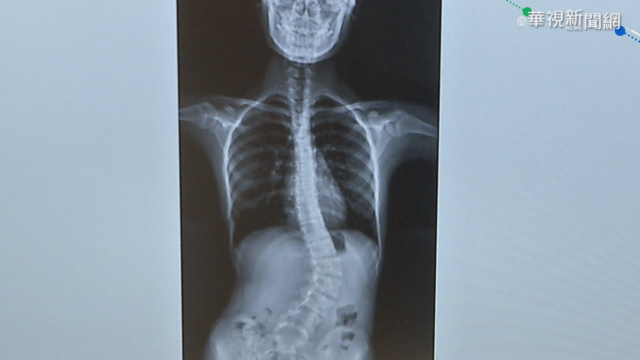

還有一位13歲的國中生也脊椎側彎,X光片上的脊椎明顯看得出呈現S型,也可以看到他的肩膀一高一低,亞大醫院復健部主治醫師林千琳說:「左側的骨盆比較高,他的右側的肩膀就會比較高。」,醫生說,脊椎側彎有分先天和後天,後天造成的原因可能是,亞大醫院復健部主治醫師林千琳說:「有的孩子寫字時(身體)會歪斜,或者是喜歡用平板(電腦),他有一些保持一個姿勢太久。」

醫師提醒,家長可以檢視小孩的肩膀是否等高,肩胛骨是否突出、骨盆有沒有對稱,以及身體前彎時其中一側背部有沒有突出,有異常的話要儘快就醫治療,不然拖愈久會惡化,還會影響身高。